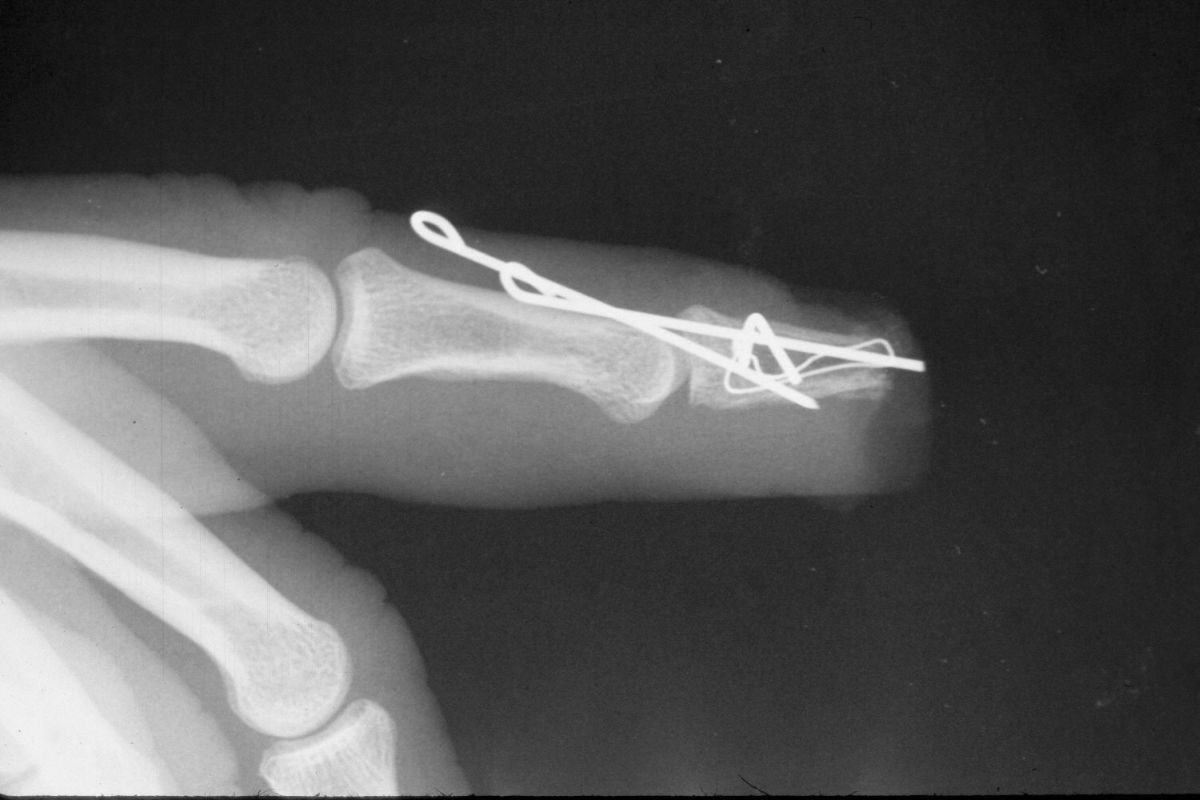

| Case

3. This gentleman sustained partial amputations of all fingers in an industrial press. His index finger was the only digit with a potentially salvageable fingertip. |

| Distal phalanx

fracture stabilization. Pins were placed to protrude

proximally in anticipation of flap cover. |